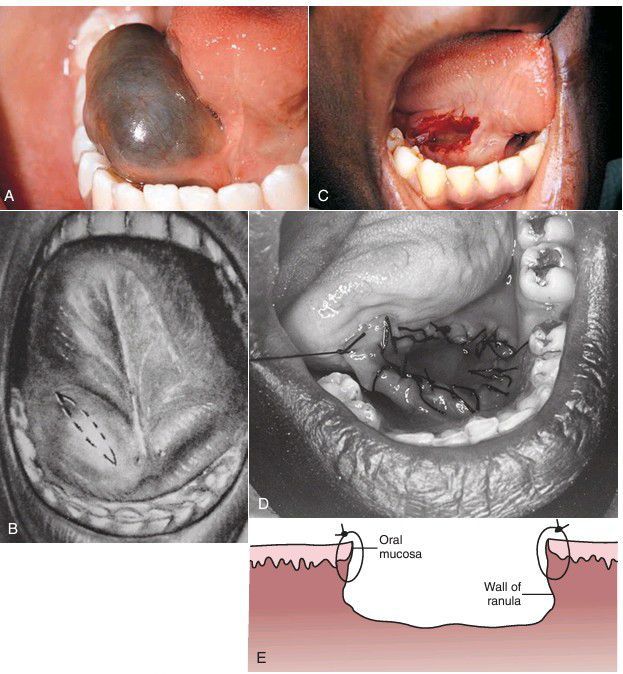

A) Ranula in the right floor of mouth from accumulation of sublingual gland saliva in soft tissue due to ruptured salivary duct. (B) Elliptical marsupialization incisions. (C) Marsupialization of ranula, with excision of oral mucosa together with the superior wall of ranula. (D) Completion of marsupialization of left floor of mouth ranula with placement of circumferential sutures. (E) Completed marsupialization with ranula lining sutured to floor of mouth mucosa.